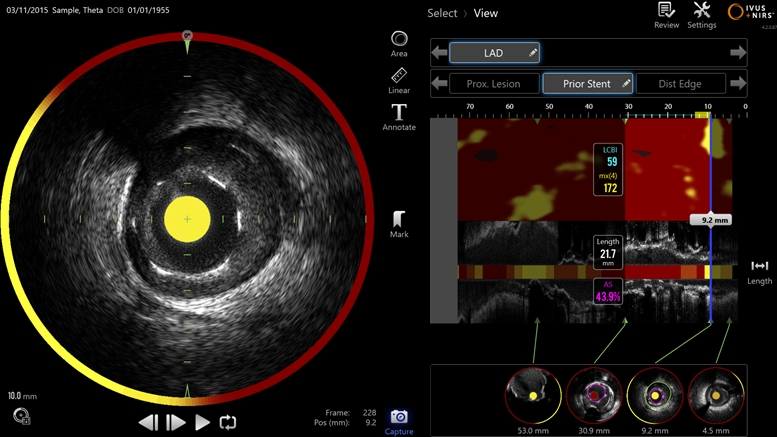

| Ultrasonic intravascular imaging is used to determine the degree to which arteries are blocked by plaques, but the specific chemical nature of those plaques is thought to be critical in deciding whether or not the blockage will lead to a serious cardiac event such as a heart attack. Infraredx's dual-mode technology combines ultrasound with near-infrared spectroscopy to detail both the blockage and its chemical make-up. Image: Infraredx. |